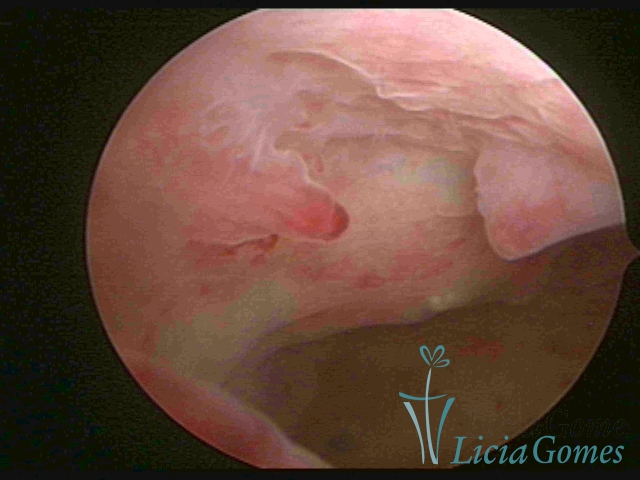

A Hiperplasia Complexa tem um aspecto pseudo polipoide, lembrando tecido cerebroide ou com reação deciduoide. A vascularização superficial é mais evidente e com vasos em formatos de saca-rolha ou espirais.

A Hiperplasia atipia e o aspecto histeroscópico são semelhantes à da hipertrofia complexa, visualizando também a vascularização com atipias. Com o aumento do calibre dos vasos superficiais, pode ser encontrado também tecido em necrose.